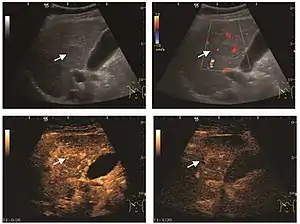

Encephaloid hepatocellular carcinoma (CEUS). Contrast tumor enhancement is observed on the left during arterial phase. The “wash-out” phenomenon can be seen on the right, during portal venous phase.

HCC appearance on 2D ultrasound is that of a solid tumor, with imprecise delineation, with heterogeneous structure, uni- or multilocular (encephaloid form). An "infiltrative" type is also described which is difficult to discriminate from liver nodular reconstruction in cirrhosis. Typically HCC invades liver vessels, primarily the portal veins but also the hepatic veins . Doppler examination detects a high speed arterial flow and low impedance index (correlated with described changes in tumor angiogenesis). The spatial distribution of the vessels is irregular, disordered. CEUS examination shows hyperenhancement of the lesion during the arterial phase. During the portal venous phase there is a specific "wash out" of ultrasound contrast agent (UCA) and the tumor appears hypoechoic during the late phase. Poorly differentiated tumors may have a stronger wash out leading to an isoechoic appearance to the liver parenchyma during portal venous phase. This appearance was found in approx. 30% of cases. The described changes have diagnostic value in liver nodules larger than 2 cm.